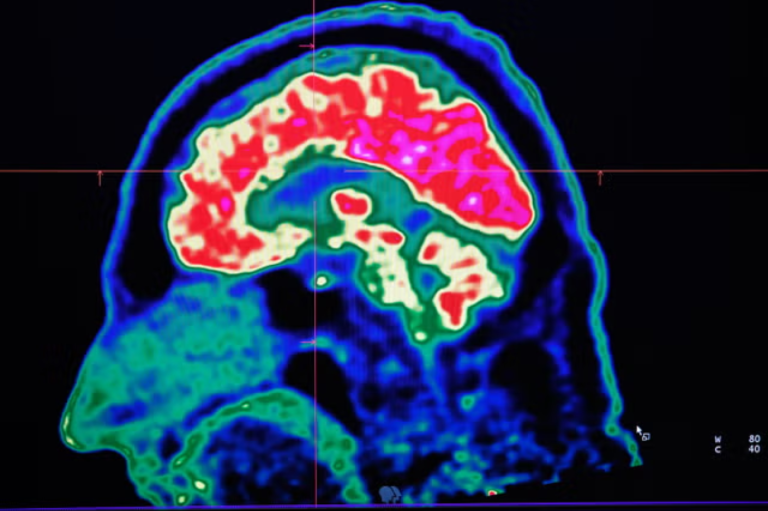

إنجاز علمي بريطاني في رصد سرطان الدماغ بفحص دم

أشاد باحثون بريطانيون بإنجاز رائد تمثل في إجراء أول اختبار دم في العالم، قادر على تشخيص أنواع محددة من سرطان الدماغ. وأوضح المتخصصون أن هذا الاختبار السهل يمكن أن يقلل الحاجة إلى إجراء عمليات جراحية – تعد خطرة في الوقت الراهن – لتشخيص بعض أورام الدماغ.

وأضافوا أن من شأن هذا النهج أن يسهم أيضاً في التشخيص المبكر للأورام الدماغية، الذي بدوره يمكن أن يسرع العلاج من جهة، وأن يزيد من جهة أخرى معدلات بقاء المرضى الذين يعانون أحد أكثر أشكال سرطان الدماغ فتكاً، على قيد الحياة.

الباحثون في “مركز التميز في أبحاث أورام الدماغ” Brain Tumour Research Centre of Excellence – الذي تديره “جامعة إمبريال كوليدج لندن”، و”مستشفى إمبريال كوليدج للرعاية الصحية” التابع لـ”هيئة الخدمات الصحية الوطنية” Imperial College Healthcare NHS Trust – أجروا دراسات أولية لتقييم دقة الاختبار في تشخيص الأورام الدبقية، بما فيها “الورم الأرومي الدبقي” Glioblastoma (GBM)، وهو النوع الأكثر انتشاراً من أورام الدماغ وأشدها فتكاً لدى البالغين، إلى جانب “الأورام النجمية” Astrocytomas و”أورام الدبقيات قليلة التغصن” Oligodendrogliomas.

اختبار الدم الذي يحمل اسم “ترينيترا – غليو” TriNetra-Glio، طورته شركة “داتار لأمراض السرطان الوراثية” Datar Cancer Genetics، من طريق عزل الخلايا الدبقية التي تنفصل عن الورم وتنتشر في مجرى الدم، ومن ثم تلوين هذه الخلايا المعزولة التي يمكن حينئذ التعرف إليها تحت المجهر.